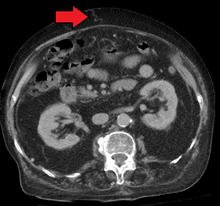

Mark.png)

The diagnosis of portal hypertension can be done via HVPG (hepatic venous pressure gradient) measurement has been accepted as the gold standard for assessing the severity of portal hypertension. Portal hypertension is defined as HVPG greater than or equal to 5 mm Hg and is considered to be clinically significant when HVPG exceeds 10 to 12 mm Hg.[9]